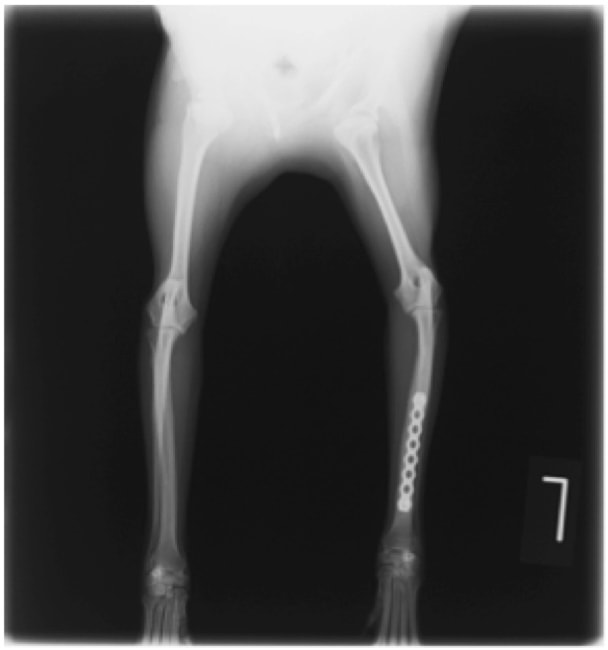

ペルシャ猫 11ヶ月齢 雄

他院にて左大腿骨遠位の成長板骨折(salter-harrisⅠ型)が認められており、治療相談を目的として来院。当院にて、キルシュナーワイヤーを用いたピンニングにより骨折部位の整復を行いました。術後の経過は良好で、現在も経過観察中です。

術前レントゲン

術後レントゲン